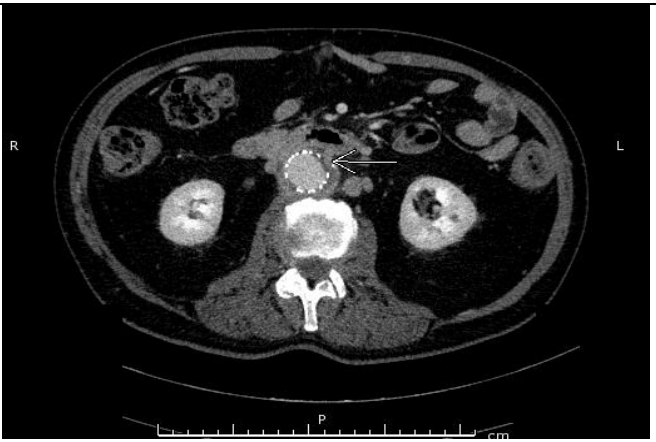

The patient was admitted with a severe IDA, confirmed by laboratory tests (Hb 4.3 g/dL, MCV 76 fl, ferritine 3 ng/ml), with no blood traces at rectal examination. Hemodynamical stability was maintained during all hospitalization; six blood transfusions was overall infused. Taking into account the previous investigations, a video capsule endoscopy (VCE) was performed showing minimal traces of red blood in the proximal small bowel lumen, without obvious mucosal lesions (Figure A). We decided to further investigate the small bowel with a per-oral device assisted enteroscopy (DAE), with identified a bulging with an adherent clot (Figure B) in the distal duodenum. The clot was gently washed with no signs of ongoing bleeding; its removal exposed a deep ulceration containing a yellowish structure behind (Figure C). An urgent angio-CT confirming the aorto-duodenal fistula (Fig. D) was performed and the patient was transferred to Vascular Surgery Department for surgical treatment.

D. Angio-CT: aorto-duodenal fistula (white arrow).

After endoscopy, since no signs of ongoing bleeding were seen and the patient remained hemodinamically stable, an urgent angio-CT confirming the aorta-duodenal fistula was performed.